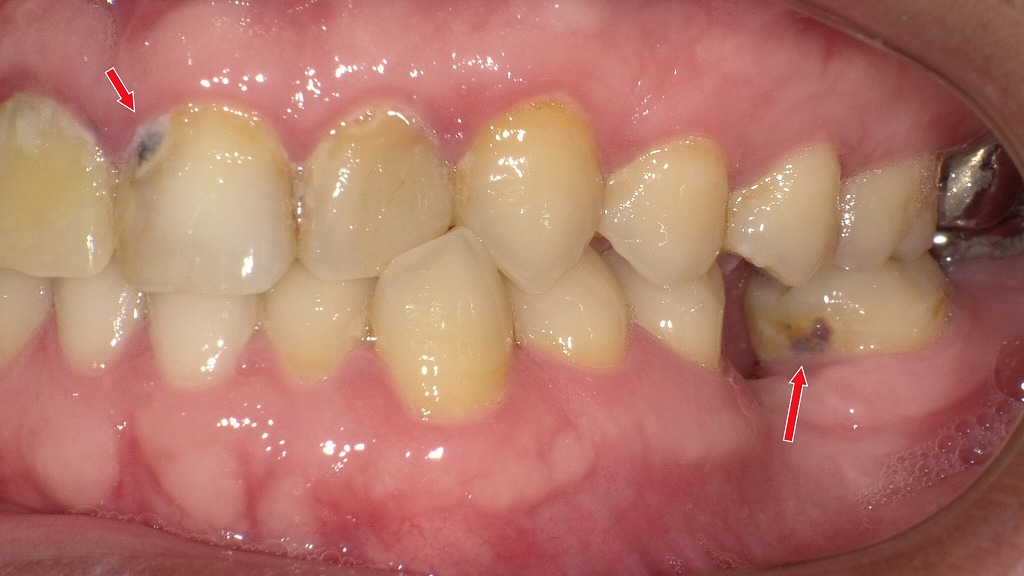

赤矢印が示すように、歯と歯の間(コンタクト部)の初期虫歯は、肉眼ではほとんど確認できません。レントゲンを撮影することで、エナメル質内部の透過像として虫歯を早期に発見できます。見た目に穴がなくても進行している場合があるため、定期的なレントゲン検査は非常に有効です。